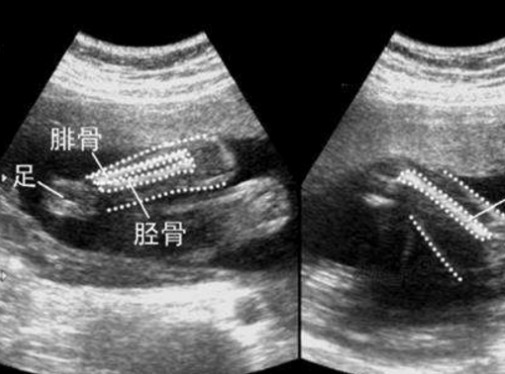

股骨长(FL)[gǔgǔcháng]是医生利用B超(或彩超)给孕妇作孕期检查时,用它来观察胎儿发育的情况常用的指标。

股骨长是大腿骨长度,肱骨长则是指上臂骨的长度。股骨长、肱骨长都是预测胎儿体质量的胎儿生物指标。不过,胎儿肱骨长在预测胎儿体质量上优于股骨长。

股骨长标准数值一般情况下是从孕13周开始计算,因为孕早期(孕1-12周)是受精卵从开始着床,到胎儿各生殖器初步发育的过程,此后各脏器才趋向完善。因此要检查股骨长建议最好从13周开始。